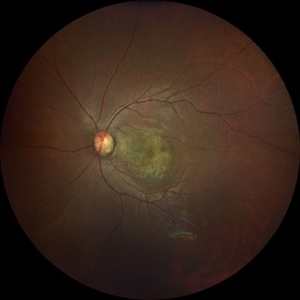

Optic disc pit

Apr 14 2023 by T. P . VIGNESH, MBBS,MS

Fundus photograph of an 32-year-old woman with optic disc pit and macular RPE atrophy .

Photographer: Bharathi S

Imaging device: ZEISS CLARUS

Condition/keywords: Optic disc pit